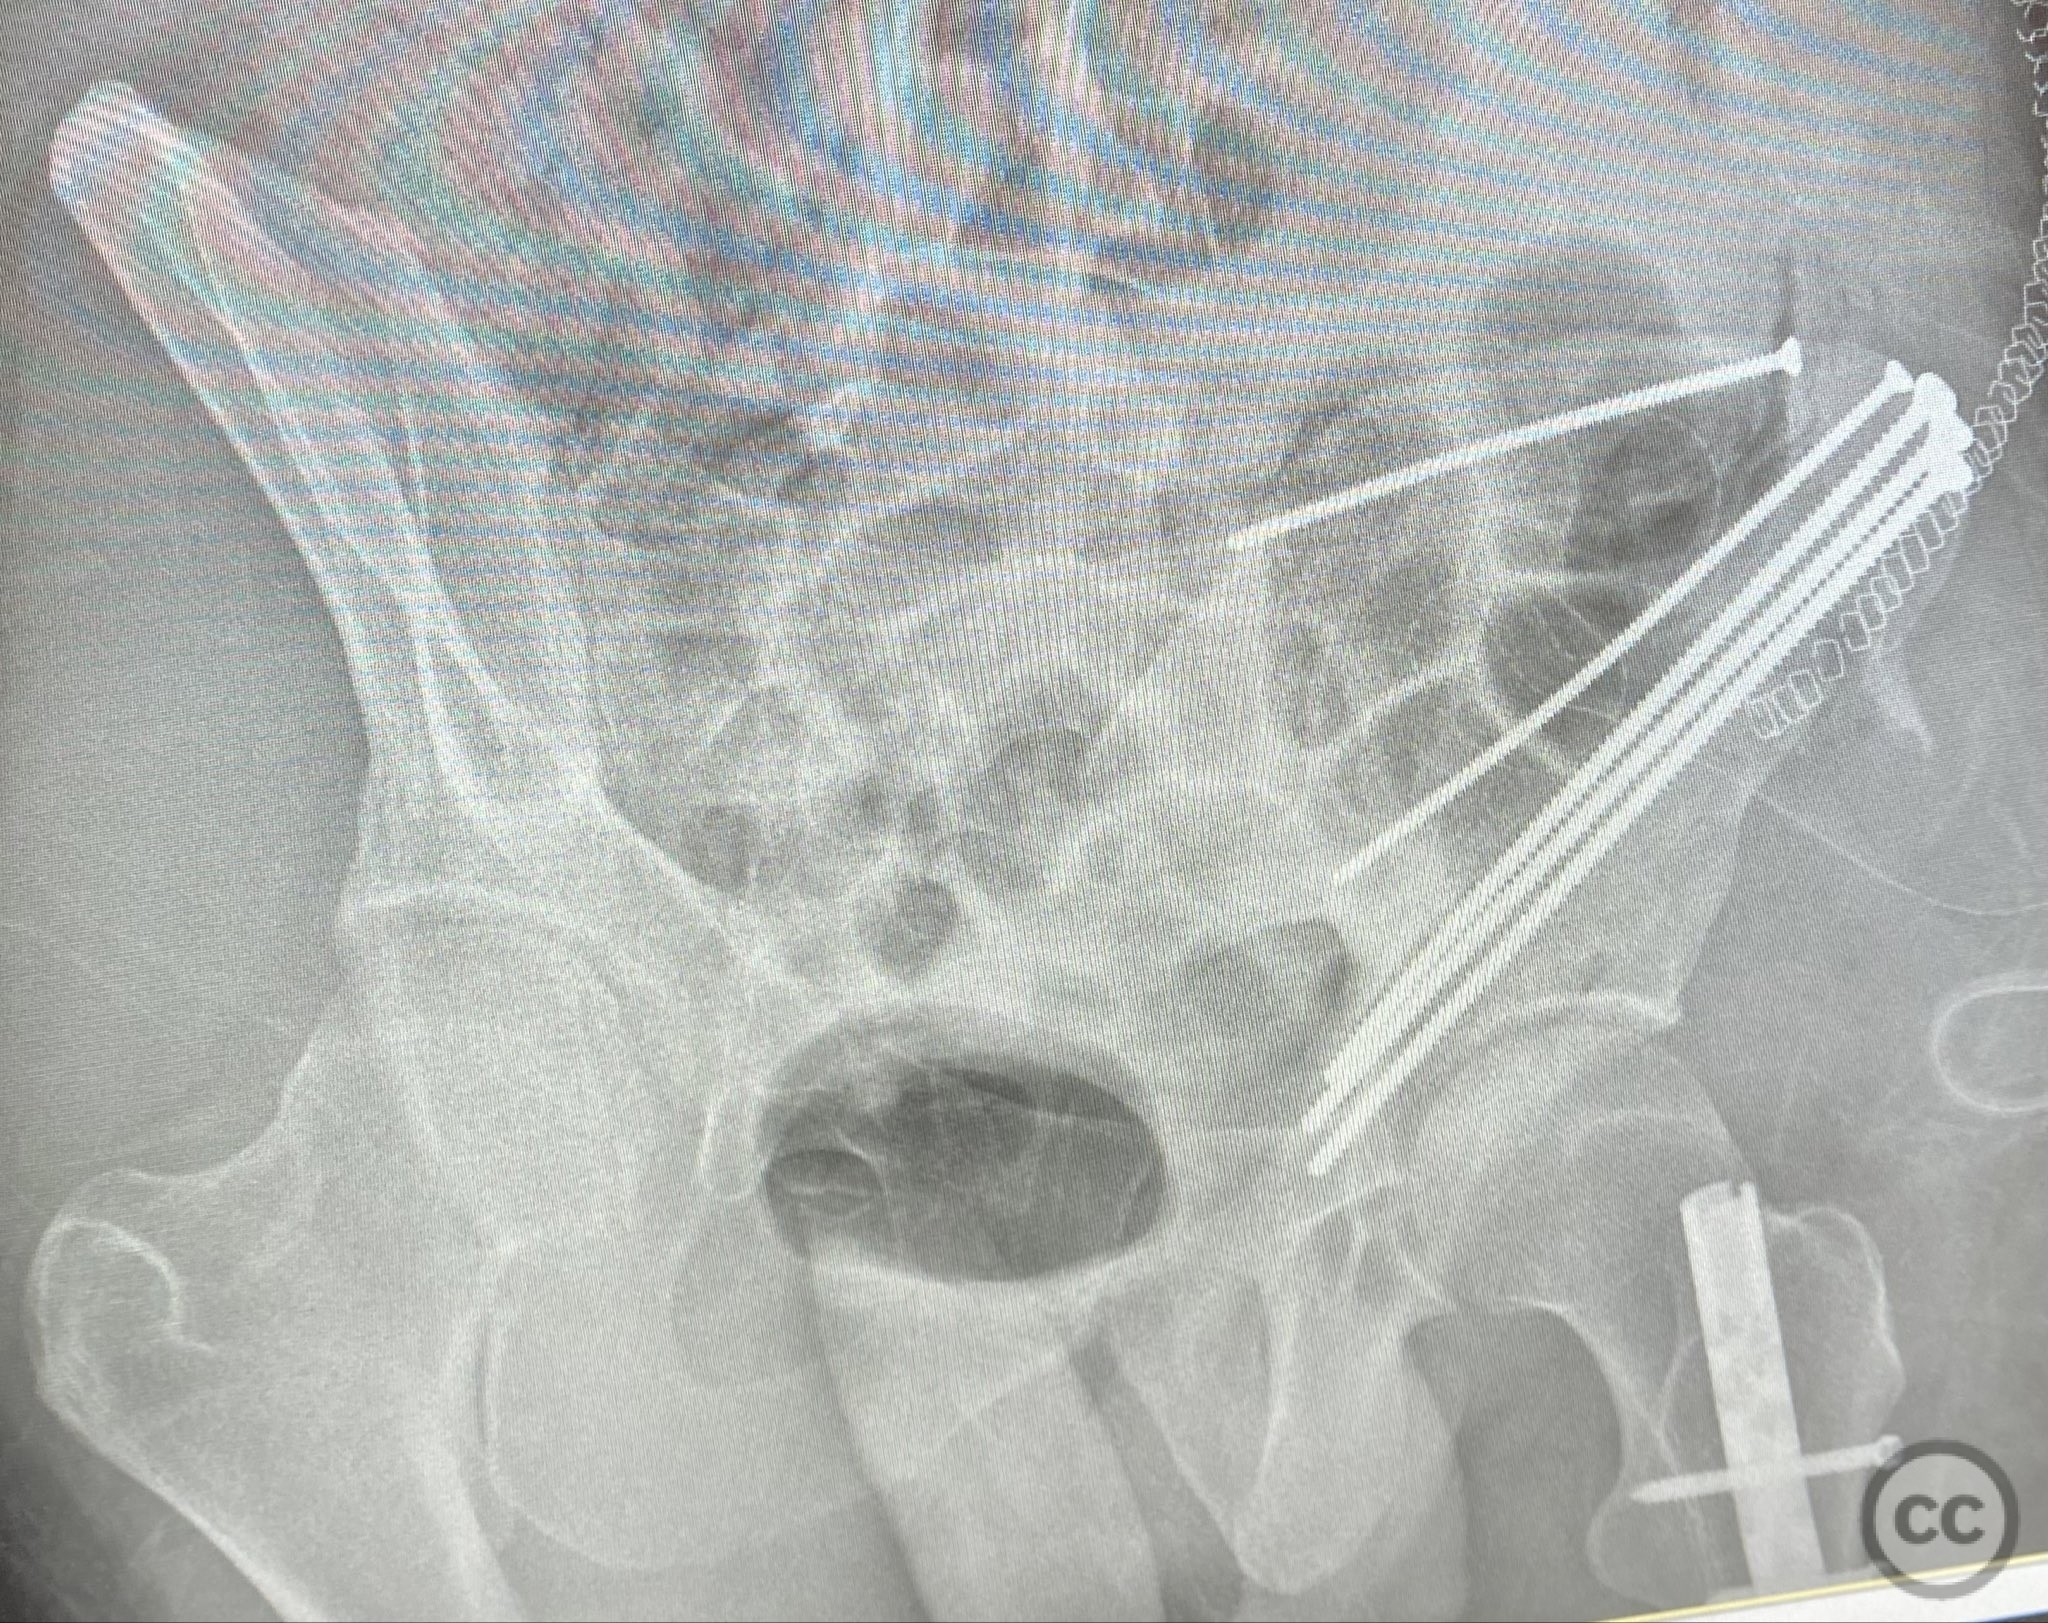

Clinical and radiological findings:  A patient sustained a high-energy injury resulting in an open, comminuted fracture of the iliac wing, sparing the pelvic ring. Associated injuries included spine, rib, and femur fractures. Initial radiographs and axial CT imaging demonstrated significant comminution of the iliac wing with intraosseous air densities indicative of an open wound. No pelvic ring disruption was identified. AO/OTA classification: 61-A2. The presence of multiple associated injuries is consistent with a direct lateral load mechanism.

Patient positioning:  The patient was positioned supine on a radiolucent table to facilitate access to the hemipelvis and allow for intraoperative imaging.

Anatomical surgical approach:  A direct lateral approach to the os ilium was performed, with incision centered over the iliac crest. Subperiosteal dissection was carried down to expose the fractured segments of the ala ossis ilii. The open wound was incorporated into the exposure for thorough irrigation and debridement. Fracture fragments were anatomically reduced and stabilized with interfragmentary lag screws placed between the inner and outer tables of the ilium.

Orthopaedic implants used:   4.5mm cortical lag screws, 3.5mm cortical lag screws